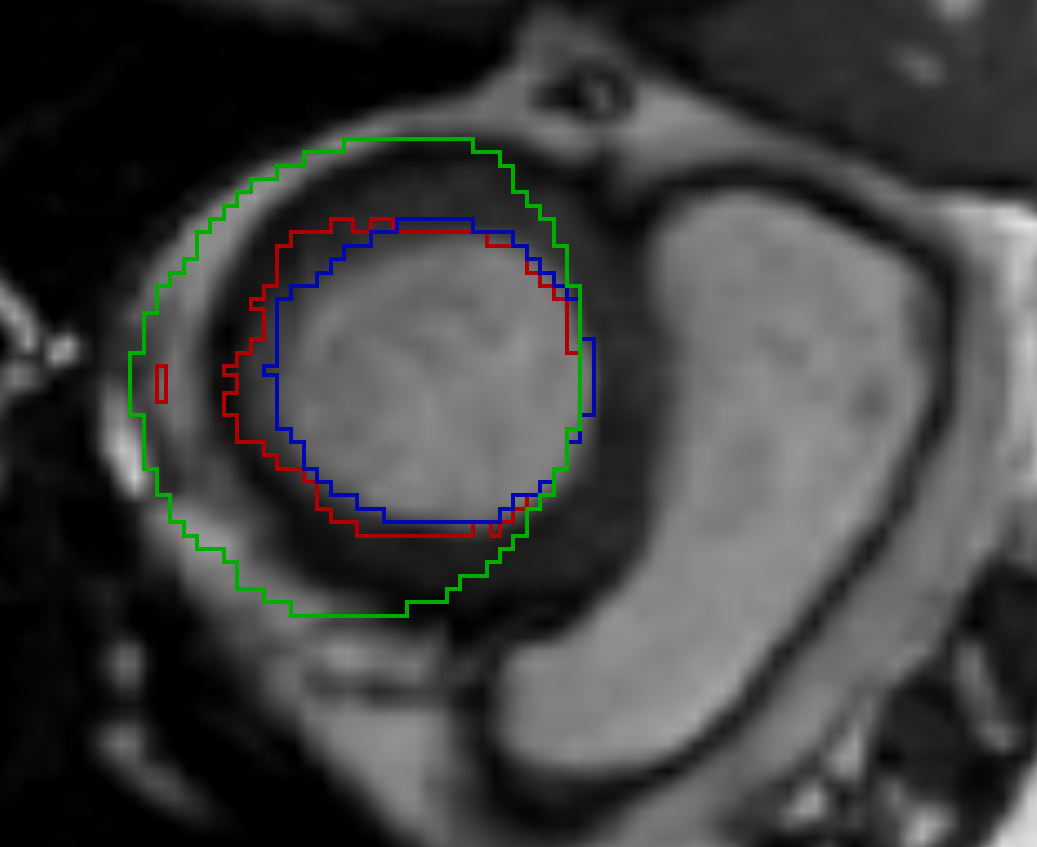

For the cardiac datasets the DVF for mapping the systolic phase to diastolic phase showed better results (DSC: 0.90, HD: 10.35 mm, ASSD: 1.49 mm) compared to the registration from diastolic to systolic phase (DSC: 0.81, HD: 13.12 mm, ASSD: 1.95 mm). We attribute this direction-dependent behaviour to the resampling of the Sunnybrook datasets. In the diastolic images the border of the LV segmentation is in the area of a high gradient in the deformation field where small and large deformations meet. Due to the nearest neighbour interpolation used for resampling the segmentation masks, the mask for interpolated slices is either too small or too large with respect to the linearly interpolated image slices. An example is shown in Fig. 3. However, to exclude an impact of the networks design we repeated the registration with switched input channels. The repeated experiments showed similar results and confirm the more accurate evaluation results from systolic to diastolic phase. Another point that contradicts a methodological failure is that for the lung datasets the better performance was distributed equally.

The initial average landmark distance between consecutive phase images was 2.25 1.55 mm for the Popi datasets and 2.19 2.02 mm for the DirLab datasets. The proposed registration algorithm could decrease the average distance to 1.24 0.90 mm and 1.54 1.31 mm, respectively. For a comparison with existing 4D registration methods we applied the publicly available method by [23] to the respiratory datasets and achieved average registration errors similar to the ones of our method: 1.56 1.42 mm for the DirLab and 1.11 0.87 mm for the Popi datasets. The construction of trajectories for voxels requires the combination of all DVF of a 4D dataset. As a consequence the registration error at the start of a trajectory gets propagated over time and increases or decreases with the combination of the different DVF. In Fig. 4 the error evolution is visualised for the three test datasets. At the beginning the mean registration error is 1.54 mm for the DirLab datasets and 1.24 mm for the Popi datasets. The error then increases to a mean of 2.58 mm for DirLab and 2.07 mm for Popi in the middle of the periodic motion. In the end of the breathing cycle the error falls to an error around 1 mm for both datasets. A similar error propagation pattern could be measured for the Sunnybrook datasets. For the Sunnybrook datasets segmentations are only available for the extreme phases, which allows only four comparisons per dataset. When starting with the end-diastolic phase a comparison in the middle of the cyclic motion to the end-systolic segmentation and in the end of the cycle motion to the original end-diastolic segmentation is possible. The same applies when starting with the end-systolic segmentation. In Fig. 4 the red dots indicate the measured DSC overlap, the red dotted line was fitted to the dots and estimates the DSC overlap for phase images without a segmentation available. Compared to a direct registration of the maximum exhale and inhale phases the registration error increased on average by 0.48 mm with the combination of the DVF. The average registration error for the extreme phases in the Popi dataset increased from 1.46 1.59 mm to 1.98 1.56 mm when we registered the whole 4D dataset instead of the two extreme phases solely. The same analysis reported an increase from 1.83 2.35 mm to 2.54 2.01 mm for the DirLab images and and decrease in the DSC from 0.86 0.10 to 0.79 0.14 for the Sunnybrook data. The DVF of the 4D evaluation showed a FoF of 0.02 % and an average Jacobi determinant of 1.00 0.06.

a) before registration

a) before registration

b) after registration

b) after registration

f) SC-N-3 contours (green: input,

blue: target, red: result)

f) SC-N-3 contours (green: input,

blue: target, red: result)